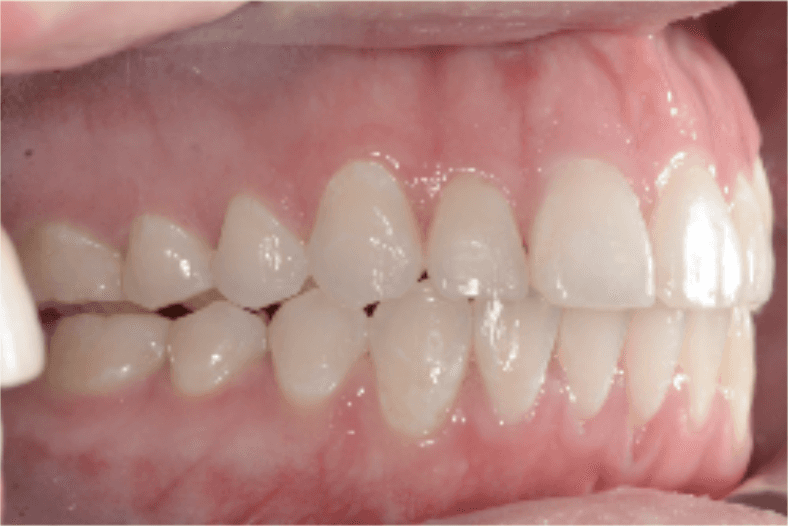

Final results

INTRAORAL